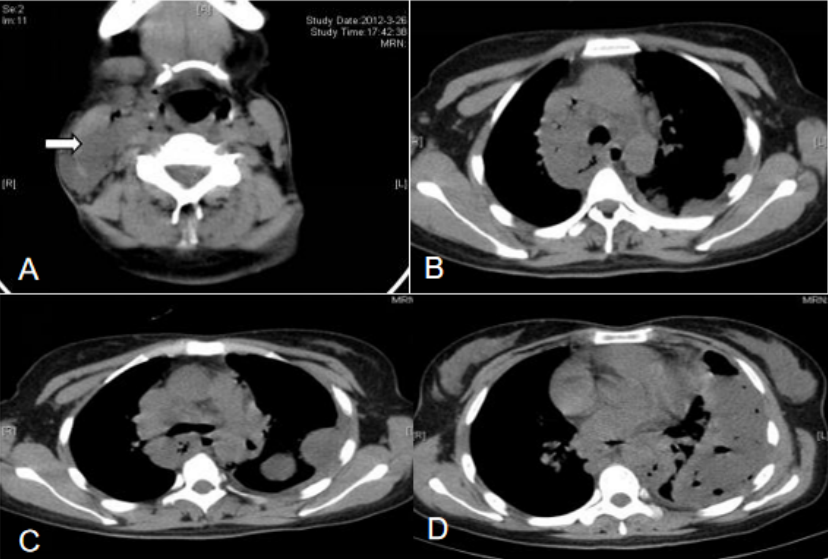

患者入住RICU后监测生命体征,予以碳酸氢钠+奥硝唑注射液胸腔冲洗;予以哌拉西林他唑巴坦+奥硝唑静滴抗感染,同时给予氧疗、补液、护肝等各脏器功能支持治疗。患者严重营养不良,吞咽困难、食欲差,恶心呕吐明显,遂给予肠内联合肠外营养支持。经治疗患者仍高热,4月3日给予经皮纵隔穿刺(图2),抽出约10 ml脓性液体。体温恢复正常3天后再次高热,PPD试验硬结直径小于5 mm,多次胸水抗酸染色未查到抗酸杆菌,多次胸水、血、穿刺液培养均阴性。调整抗感染方案为利奈唑胺+头孢噻利,仍有反复高热,调整抗生素为利奈唑胺+比阿培南,4月12日复查胸部CT考虑可能纵隔脓肿未引流尽,且左下肺积液有包裹(图3),建议患者外科行胸腔镜治疗,患者家属拒绝,故于4月17日行CT引导下经皮胸腔脓肿穿刺抽液,抽出约30 ml暗红色液体,患者体温降至38℃左右,拔除胸腔闭式引流管。患者体温逐渐恢复正常,5月7日再次予左侧包裹脓腔行B超引导下穿刺抽液,抽出约60 ml淡红色液体。5月16日出院后口服抗生素2周。6月14日复查胸部CT吸收理想(图4)。注:A、B、C为右侧颈部、纵隔脓肿及左侧胸腔积液较前吸收,D为左下肺仍有包裹性积液图4 复查胸部CT病灶基本吸收(2012-06-14)